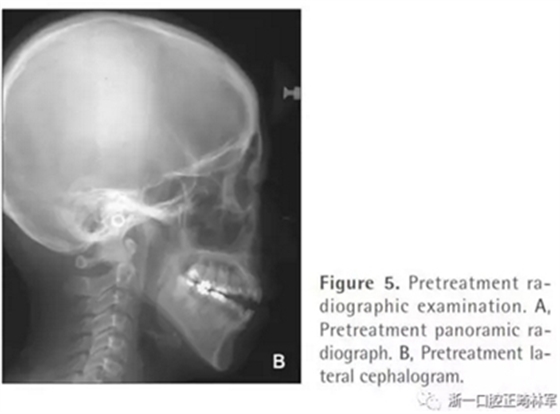

全景片顯示四顆智齒都存在,上頜切牙有牙根吸收,并且在雙側髁突都有相當大的吸收(Figures 1B and 5A)。頭測分析顯示:ANB angle, 4.5°; FMA, 46.7°; U1-SN, 95.8°; L1-MP, 83.7°(Table 1, Figure 5B)。